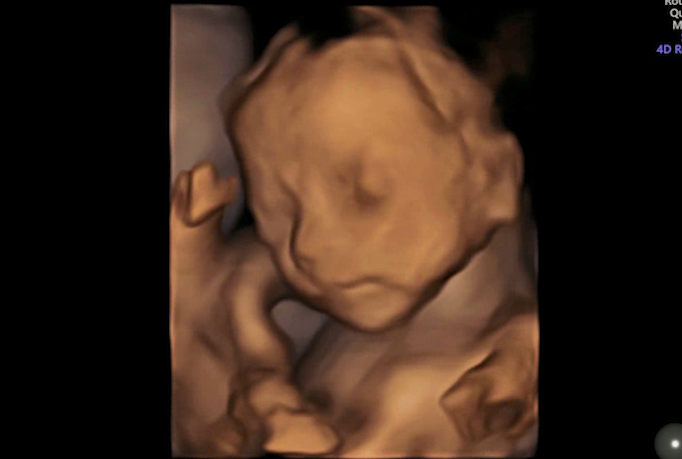

看到了宝宝的小模样

有一部分宝妈还提前感受到了小宝宝的顽皮